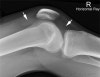

4) Very Large

This elderly patient fell onto her right knee.

She has sustained a fractured patella and has a very large knee joint effusion (arrowed).